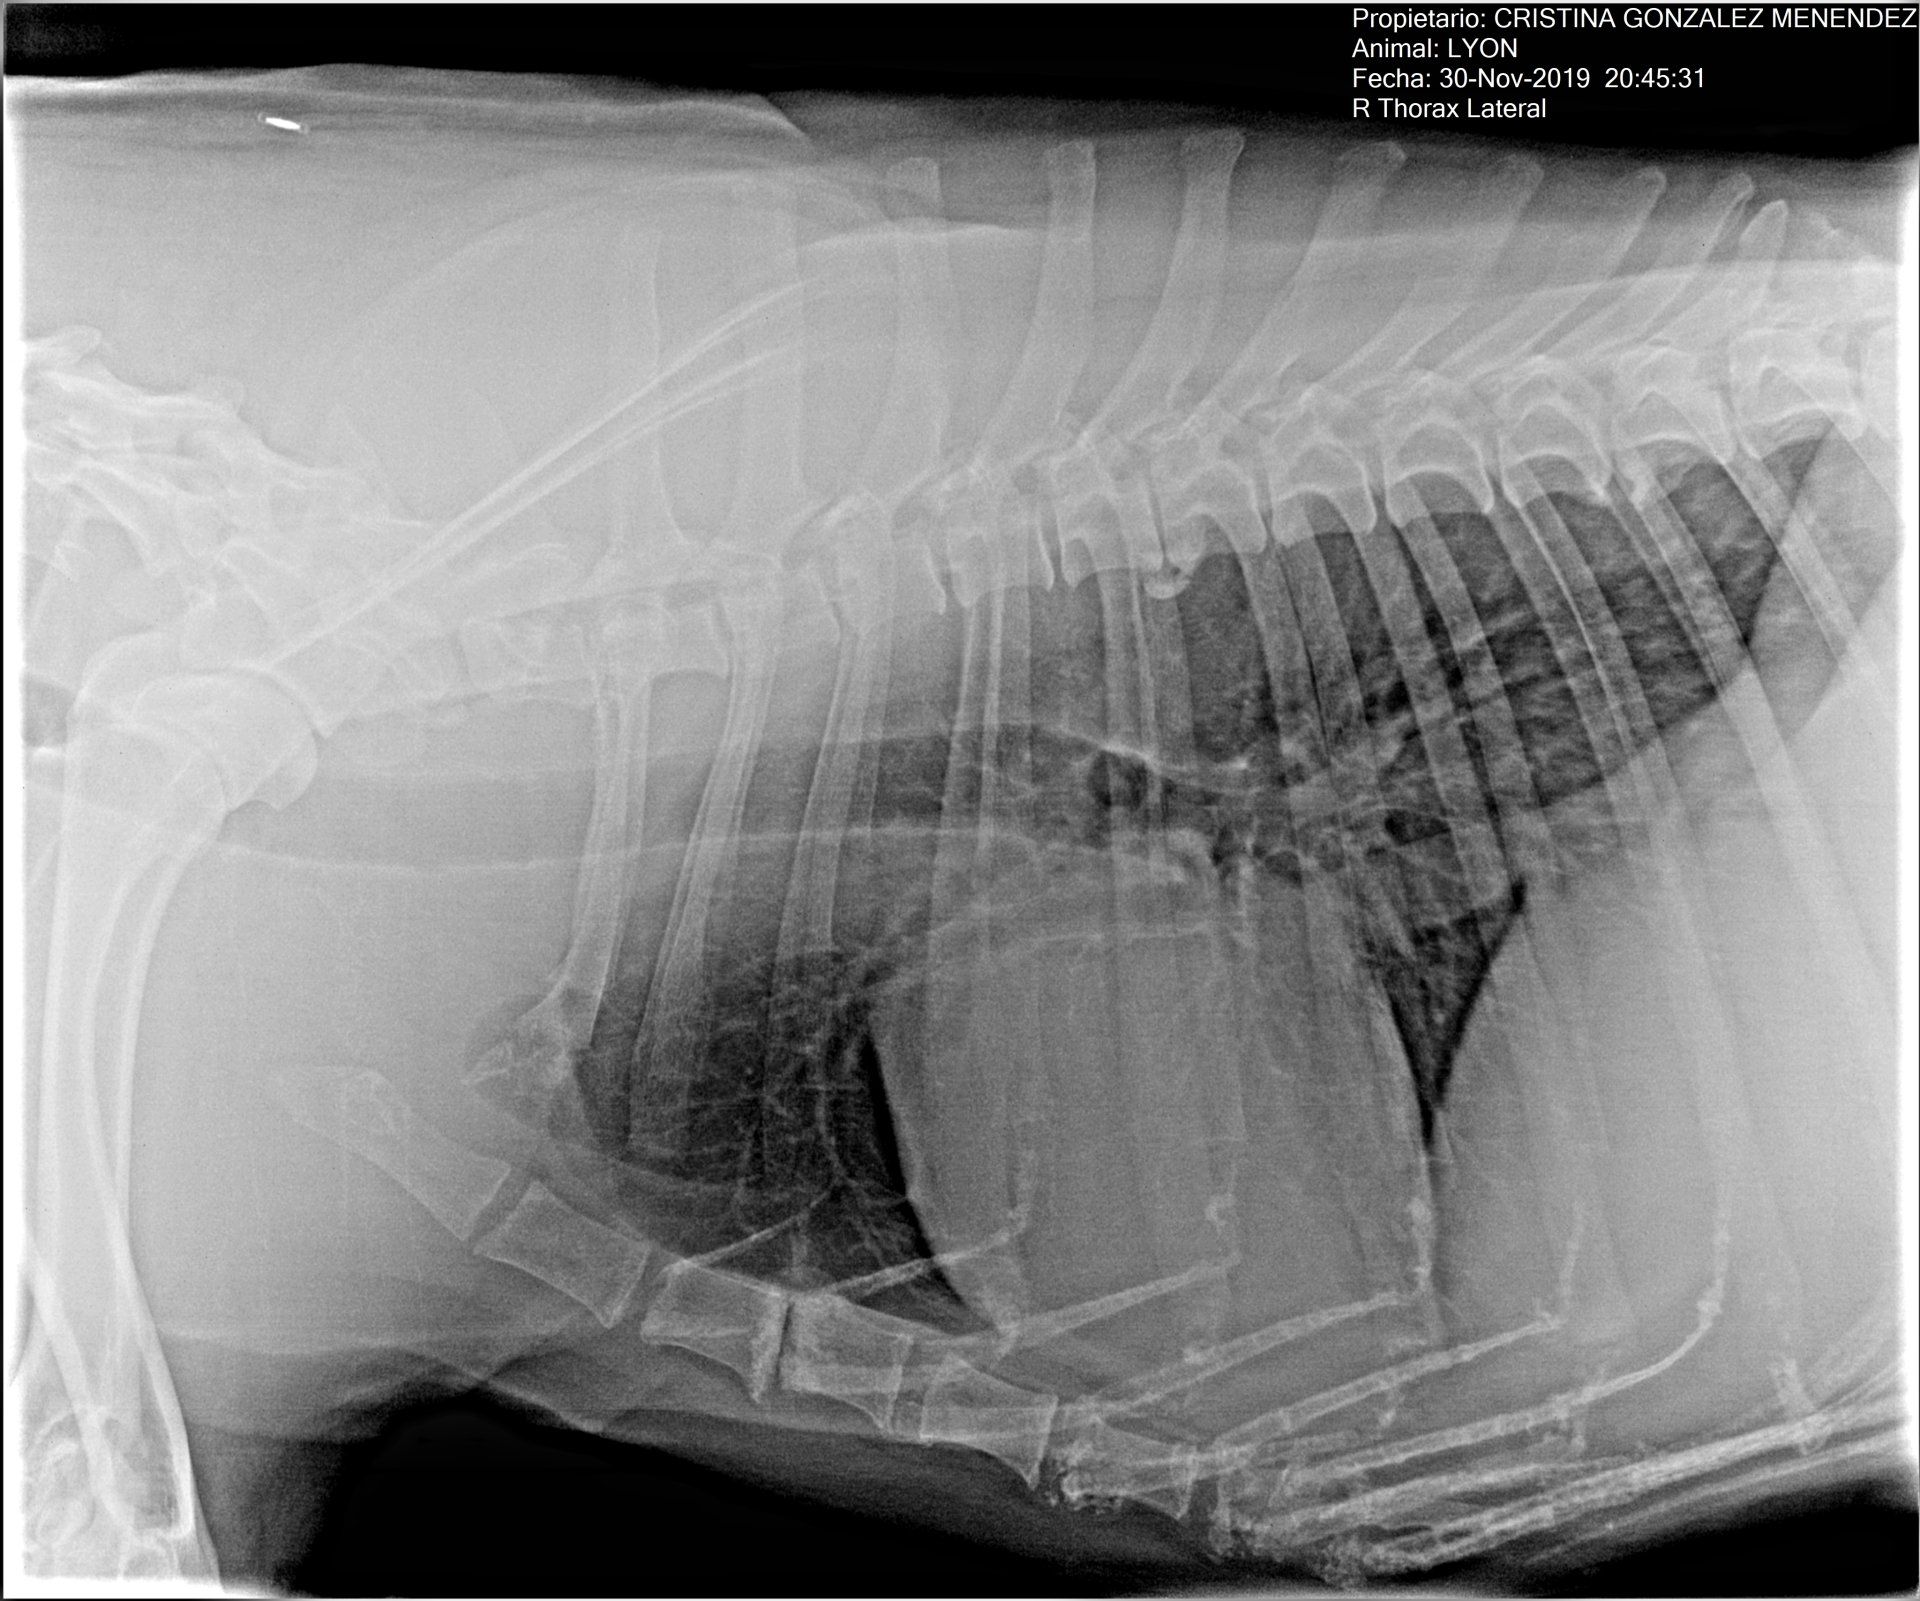

Los rayos X y la ecografía son técnicas diagnósticas complementarias. La utilidad más conocida de los rayos X, aunque evidentemente no la única, es el diagnóstico de fracturas y otras alteraciones de los huesos. Esta técnica es la más indicada por ejemplo para el diagnóstico de patologías de los pulmones. En cambio, la ecografía es indispensable para valorar el estado de los órganos del abdomen y por supuesto detectar patologías cardiacas.